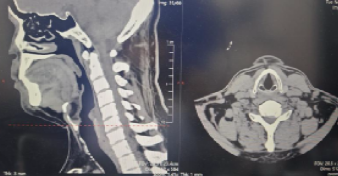

患者为 50 岁男性,3 个月前无明显诱因出现左上臂外侧、前臂背侧麻木胀痛,伴颈肩部酸痛不适,偶有行走不稳症状。在外院就诊时,颈椎 MR 检查提示 “颈椎生理曲度变直,颈椎增生,颈 6-7 终板变性,颈6-7椎间盘突出神经受压”,经保守治疗后症状无改善,为寻求进一步精准治疗来到我院。

入院后,骨科团队为患者进行了详细查体,发现其颈椎生理曲度变直,左侧颈肩部肌肉压痛阳性,左前臂背侧感觉减退,四肢肌力虽正常,但神经根受压症状明确,结合影像学检查结果,最终确诊为 “神经根型颈椎病”。考虑到患者保守治疗效果不佳,且症状已影响生活质量,患者较轻,团队经充分评估后,决定摒弃传统前路开放融合手术,采用后路微创内镜技术为其实施减压。

内镜下颈椎后路手术一项脊柱外科高精尖的微创技术,技术难度大、风险高、学习曲线长,为了不断提高技术,采众家所长,确保手术安全与效果,我院骨科脊柱外科团队特别邀请国内脊柱微创AUSS 技术创始人,云南昆明医科大学第一附属医院宋恩教授进行手术演示。手术于 2023 年 11 月 23 日在全身麻醉下进行,采用先进的 AUSS 技术,通过内镜下精准操作,顺利完成颈 6-7 椎间盘切除及神经减压。